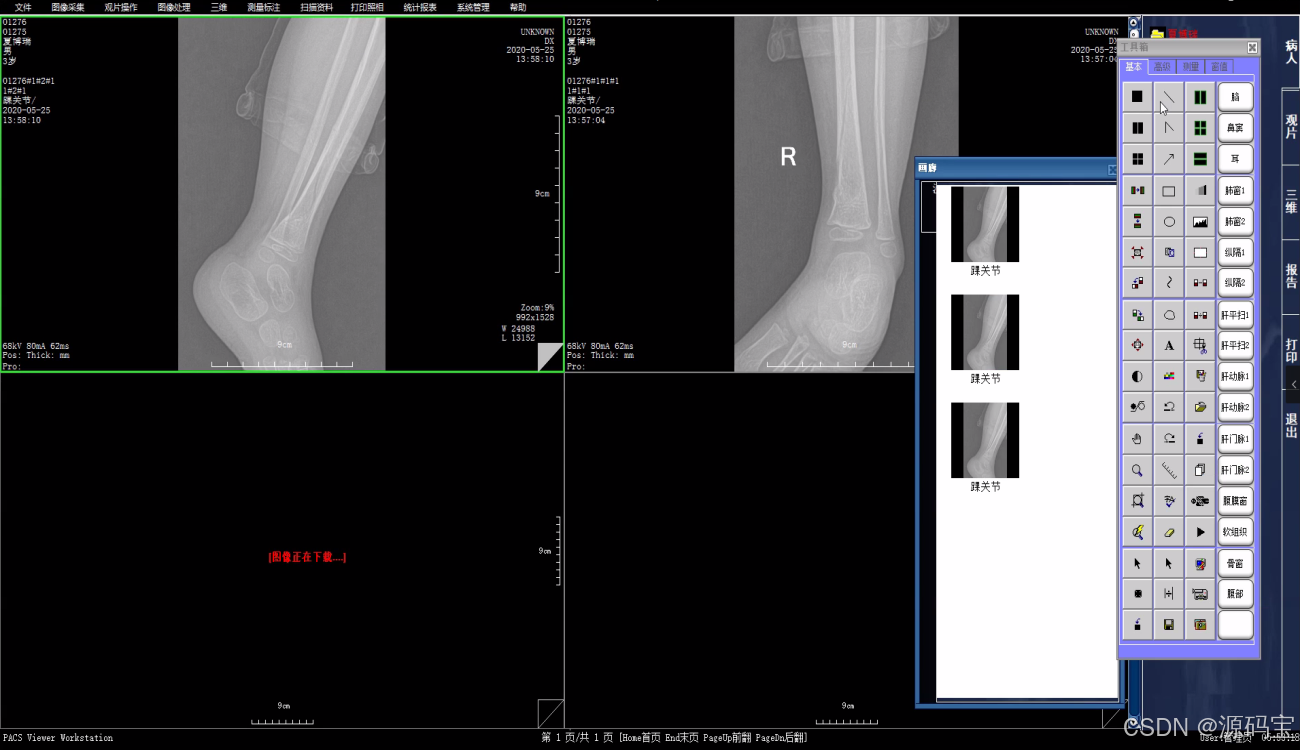

3、浏览图像

搜索到病人的影像信息后,可以在PACS系统中浏览和查看这些影像。系统会自动将病人的影像分成多个部位,可以根据需要选择浏览。

4、标记和测量

在查看影像时,可以使用系统提供的标记和测量工具对病人的影像进行标记和测量,以便更好地分析和诊断。